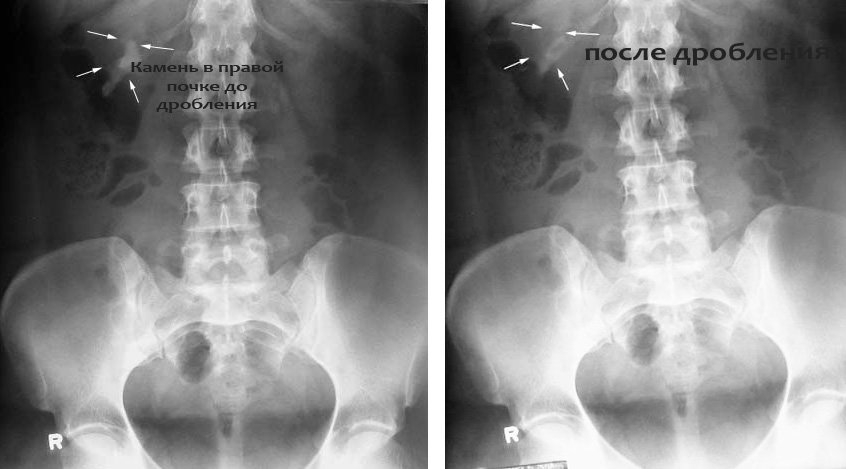

Изображения КТ конкрементов мочевого пузыря